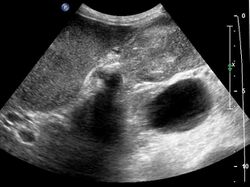

Early diagnosis is not generally possible. People at high risk, such as women or Native Americans with gallstones, are evaluated closely. Transabdominal ultrasound, CT scan, endoscopic ultrasound, MRI, and MR cholangio-pancreatography (MRCP) can be used for diagnosis. A large number of gallbladder cancers are found incidentally in patients being evaluated for cholelithiasis, or gallstone formation, which is far more common.[13] A biopsy is the only certain way to tell whether or not the tumorous growth is malignant.[14]